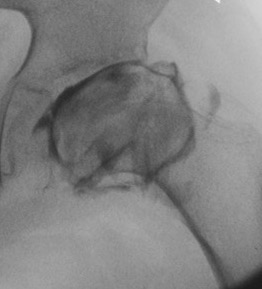

Salter pelvis osteotomy

Concept

Redirects acetabulum to provide coverage for anterolateral head

Smith Peterson approach

- iliac apophysis split

- release direct head of rectus and psoas tendon

- subperiosteal dissection to sciatic notch reflecting gluteals

Osteotomy

- through greater sciatic notch to between ASIS and AIIS

- Gigli saw passed around greater sciatic notch

- osteotomy posterior to anterior

- acetabulum rotated anteriorly and laterally

- 15 mm triangular graft from iliac crest apophysis

- secure with K wire fixation

Repair split in iliac apophysis